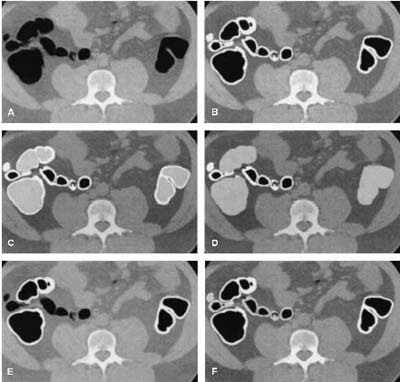

![]() |

| Axial view of (A) original slice; (B) segmented colon obtained by anatomy-based extraction (white region); (C) segmentation of colonic lumen by volume growing (light gray); (D) expansion of the segmented colonic lumen; (E) intersection of the regions segmented by ABE and colon-based analysis (CBA) (white); (F) simultaneous representation of the final knowledge-guided colon segmentation (white), and the regions removed from the ABE (light gray). Image and caption reproduced courtesy of the Journal of Computer Assisted Tomography. |